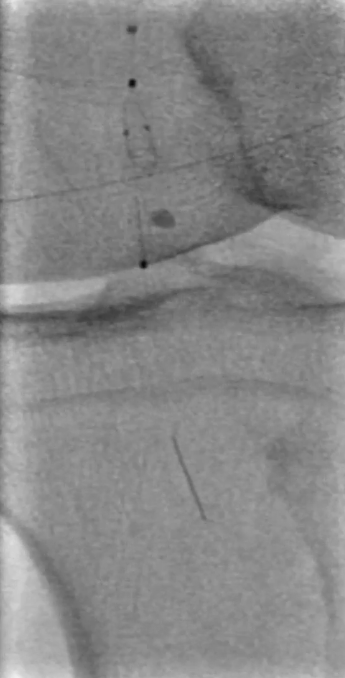

操作要点:在路径图引导下,使用超滑导丝配合6F导管选择进入支架近端(避免导丝从支架网眼穿出),随后采用新型超声开通导管尝试开通病变段。

器械优势:超声导管头端可发射超声波,能轻松通过坚硬闭塞部分;

注意事项:该导管硬度较大、方向选择性差,需配合V18导丝引导,推进时需缓慢操作并密切关注患者疼痛等不良反应。

调整与确认:开通至股浅动脉中段后,发现导丝向另一个方向打弯,退回后重新选择路径,最终顺利送至股浅动脉远端真腔,造影证实开通成功。